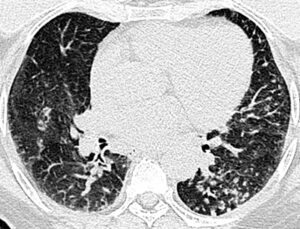

Tomografía computarizada de tórax con contraste IV

Haz click en las imágenes para verlas ampliadas

Hallazgos radiológicos

A

Opacidades lineales y nodulares basales izquierdas

B

Opacidades nodulares basales izquierdas

C

Opacidades lineales bilaterales, y nodulares basales izquierdas

D

Opacidades nodulares basales bilaterales